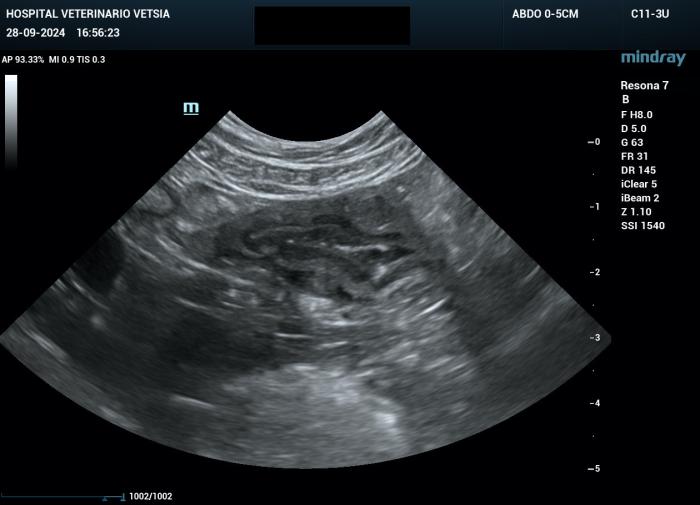

La ecografía abdominal evidenció un engrosamiento moderado de la mucosa y de la submucosa, y leve de la capa muscular del yeyuno y del íleon, generando un efecto masa transmural (Figura 2A-B).

Figura 2A-B. Imágenes ecográficas en las que se aprecia un engrosamiento de la mucosa y submucosa yeyunal, con alteración asimétrica de la capa muscular.

La grasa mesentérica adyacente se mostró moderadamente hiperecogénica, y se identificó una escasa cantidad de líquido libre, insuficiente para toma de muestra.